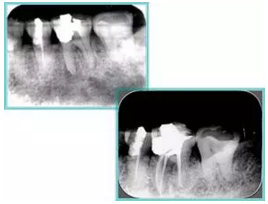

5. 不良根管充填物

常見不良根管充填物有干髓、塑化、塑化 + 根充和不良根充。

( 1 )干髓。

干髓治療時,開髓后髓腔里注入甲醛甲酚 FC 灌髓,三聚甲醛固定,髓室底放置三聚甲醛緩慢釋放,進(jìn)行根管無害化處理。髓腔緩慢壞死,機(jī)體代償出現(xiàn)根管鈣化。如果患者在封閉腔出現(xiàn)出現(xiàn)病變,由于髓腔鈣化,根管堵塞嚴(yán)重,檢查治療比較困難。

上圖為干髓治療后牙齒,齲齒疏通后進(jìn)行根管充填。

( 2 )塑化

傳統(tǒng)的治療思維:塑化治療后患者需將塑化液清理干凈,達(dá)到徹底根管治療目的。

目前的治療思維:以前塑化治療效果好時不必清理干凈塑化液。對于根尖沒有病變的患者,可借助溶解劑建立通路;根尖存在病變的患者往往是塑化治療不理想患者,需要徹底打通通路。

( 3 )塑化 + 根充。

如圖為塑化加根充處理后牙齒 X 線片。

( 4 )不良根充。

不良填充與操作有關(guān),采用輔助放大設(shè)備可有效預(yù)防不良填充